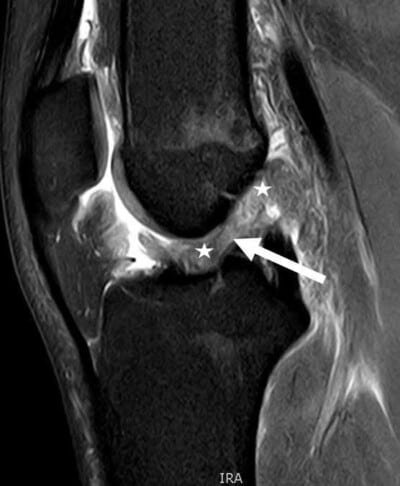

يقوم د. هشام عبد الباقي بإجراء فحص سريري دقيق مدعوم بتصوير الرنين المغناطيسي لتأكيد التشخيص وتحديد درجة الإصابة بدقة.

يمتاز بأسلوبه الدقيق في التشخيص، حيث يعتمد على الفحص الإكلينيكي الدقيق والتصوير بالرنين المغناطيسي لتحديد طبيعة الإصابة بدقة قبل وضع خطة العلاج.